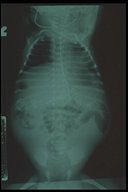

Meconium peritonitis. A classical abdominal X-ray demonstrates calcified extravasated meconium in the peritoneal cavity since fetal growth. Free air in the abdomen (football sign) is also noted.